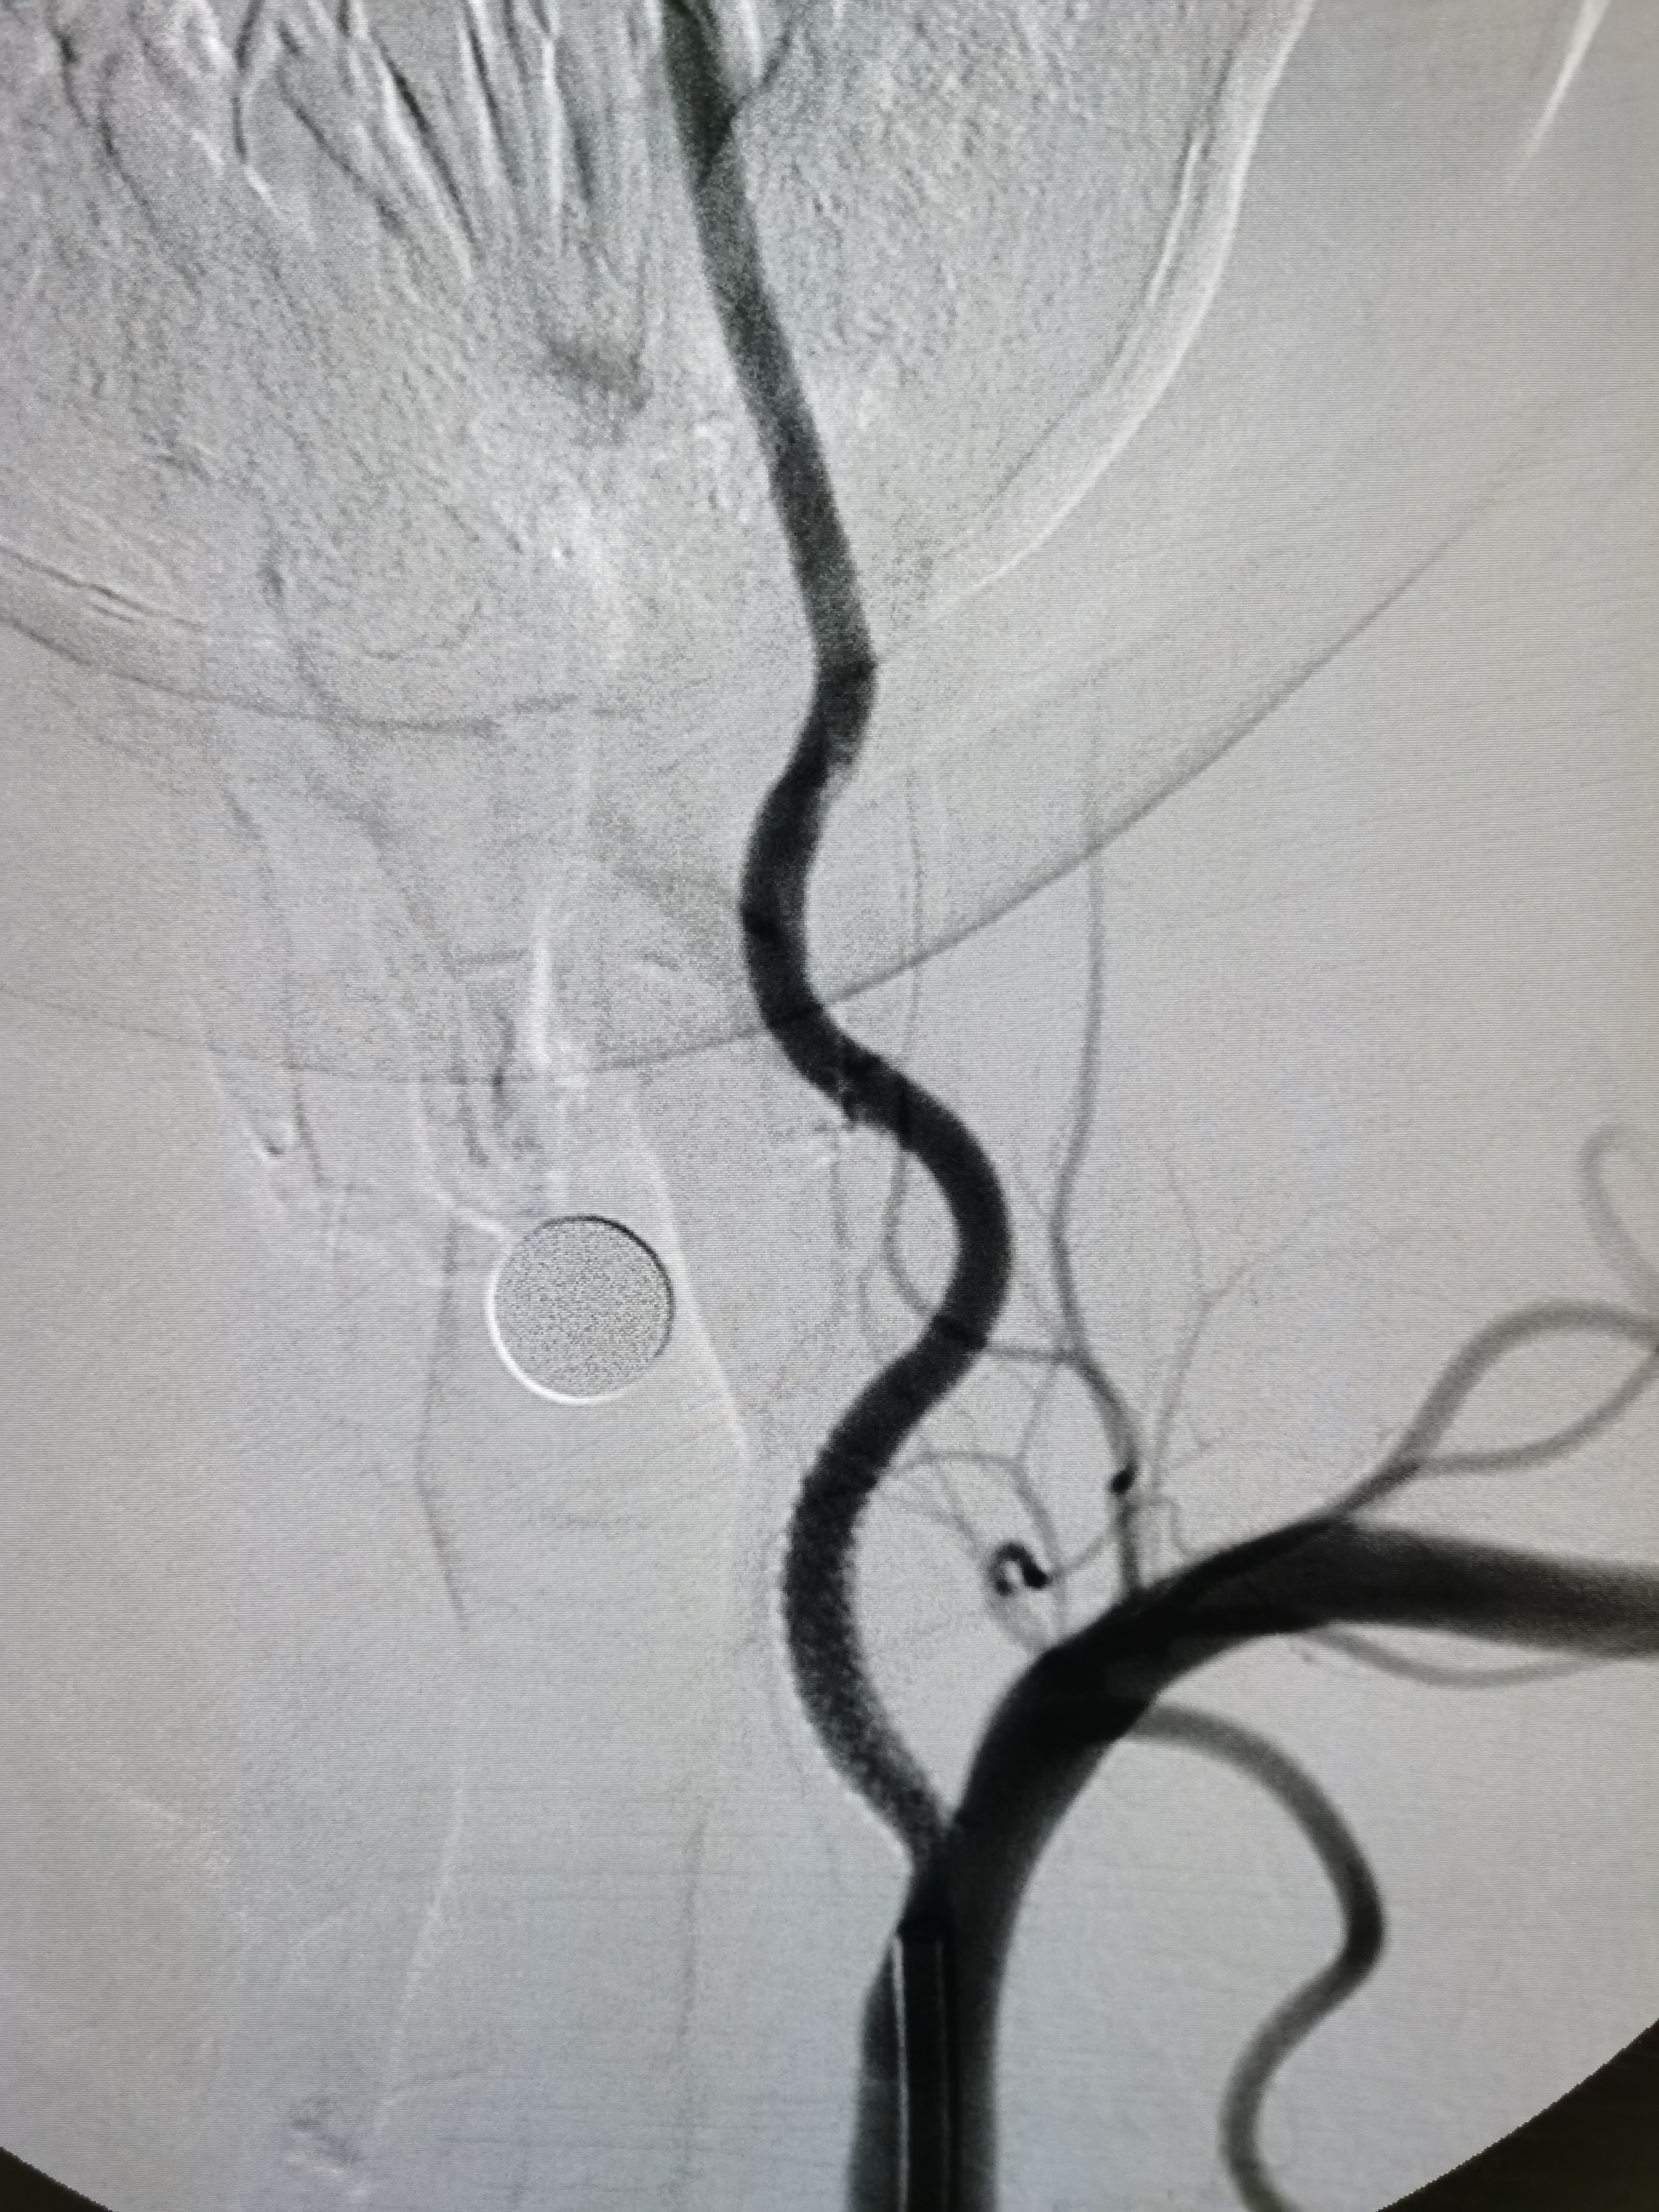

将8F导引导管送至左侧锁骨下动脉近左椎动脉起始部,微导丝顺利通过病变,2.0/20球囊预扩病变。

3、手术过程中,先用小球囊扩张病变,观察血栓情况,及时应用支架全程覆盖血栓及病变部位,成形满意。